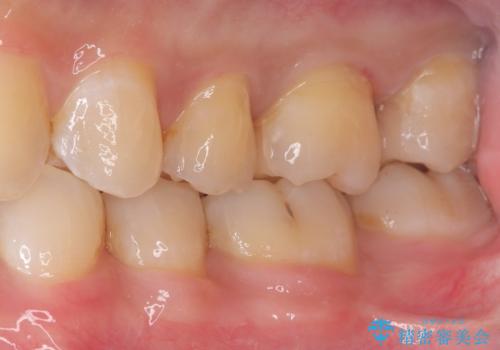

初診でいらした患者様で、口腔内を確認したところ左上6番目と7番目の歯の接する面を中心に両方の歯に虫歯が認められたため、セラミックインレーでの修復治療となりました。

左上6番の歯には元々修復物が入っていましたが、それも一度除去し新たにMOD窩洞のセラミックインレーをセットしました。

左上7番咬合面裂溝の着色部分は今後エアフロー等を使用し落としていく予定です。

セラミックインレーセット時はラバーダム防湿を行っています。